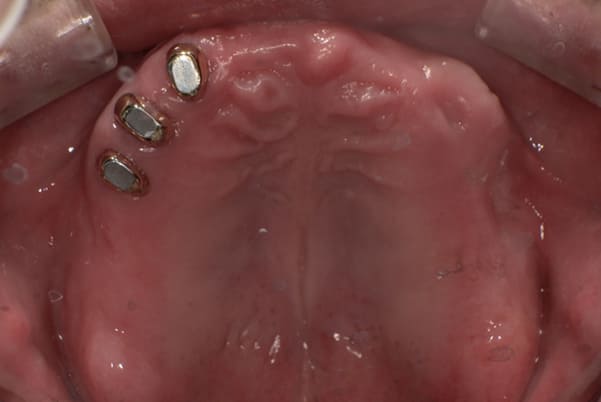

症例レポート[CASE.09]

下の入れ歯は

痛くて使わなくなった

- 男性(50代)

- 上の入れ歯が外れ食事ができない、痛い。下の歯が膿んで腫れて痛い、下の入れ歯は痛くて使わなくなった。

- 上顎精密金属床総入れ歯

- 下顎精密金属床総入れ歯

- 磁性アタッチメント(白金加金) 2歯

歯周病により歯はぐらぐらで歯茎は腫れた状態です。かみ合わせも、もともと受け口で下の歯が前にでているのが分かります。

治療後は、入れ歯により受け口も治し正常のお口元に。

治療前は上の入れ歯の歯のラインが湾曲し、下の歯が前に出ているのが分かります。

治療後は、歯のラインが真っすぐとなり、下の歯も正常のかみ合わせになっています。

金属を用いた総入れ歯の欠点に、歯茎がやせ、外れやすくなった際、裏打ちをする修理が困難であることが挙げられます。

しかし、右のお写真のように、後ろのみプラスチックを用いることで、金属を用いた場合と同じ装着感は保ったまま、プラスチック部を裏打ちすることで、入れ歯が外れにくいよう修理が可能となります。

受け口も改善され、自然なお口元に